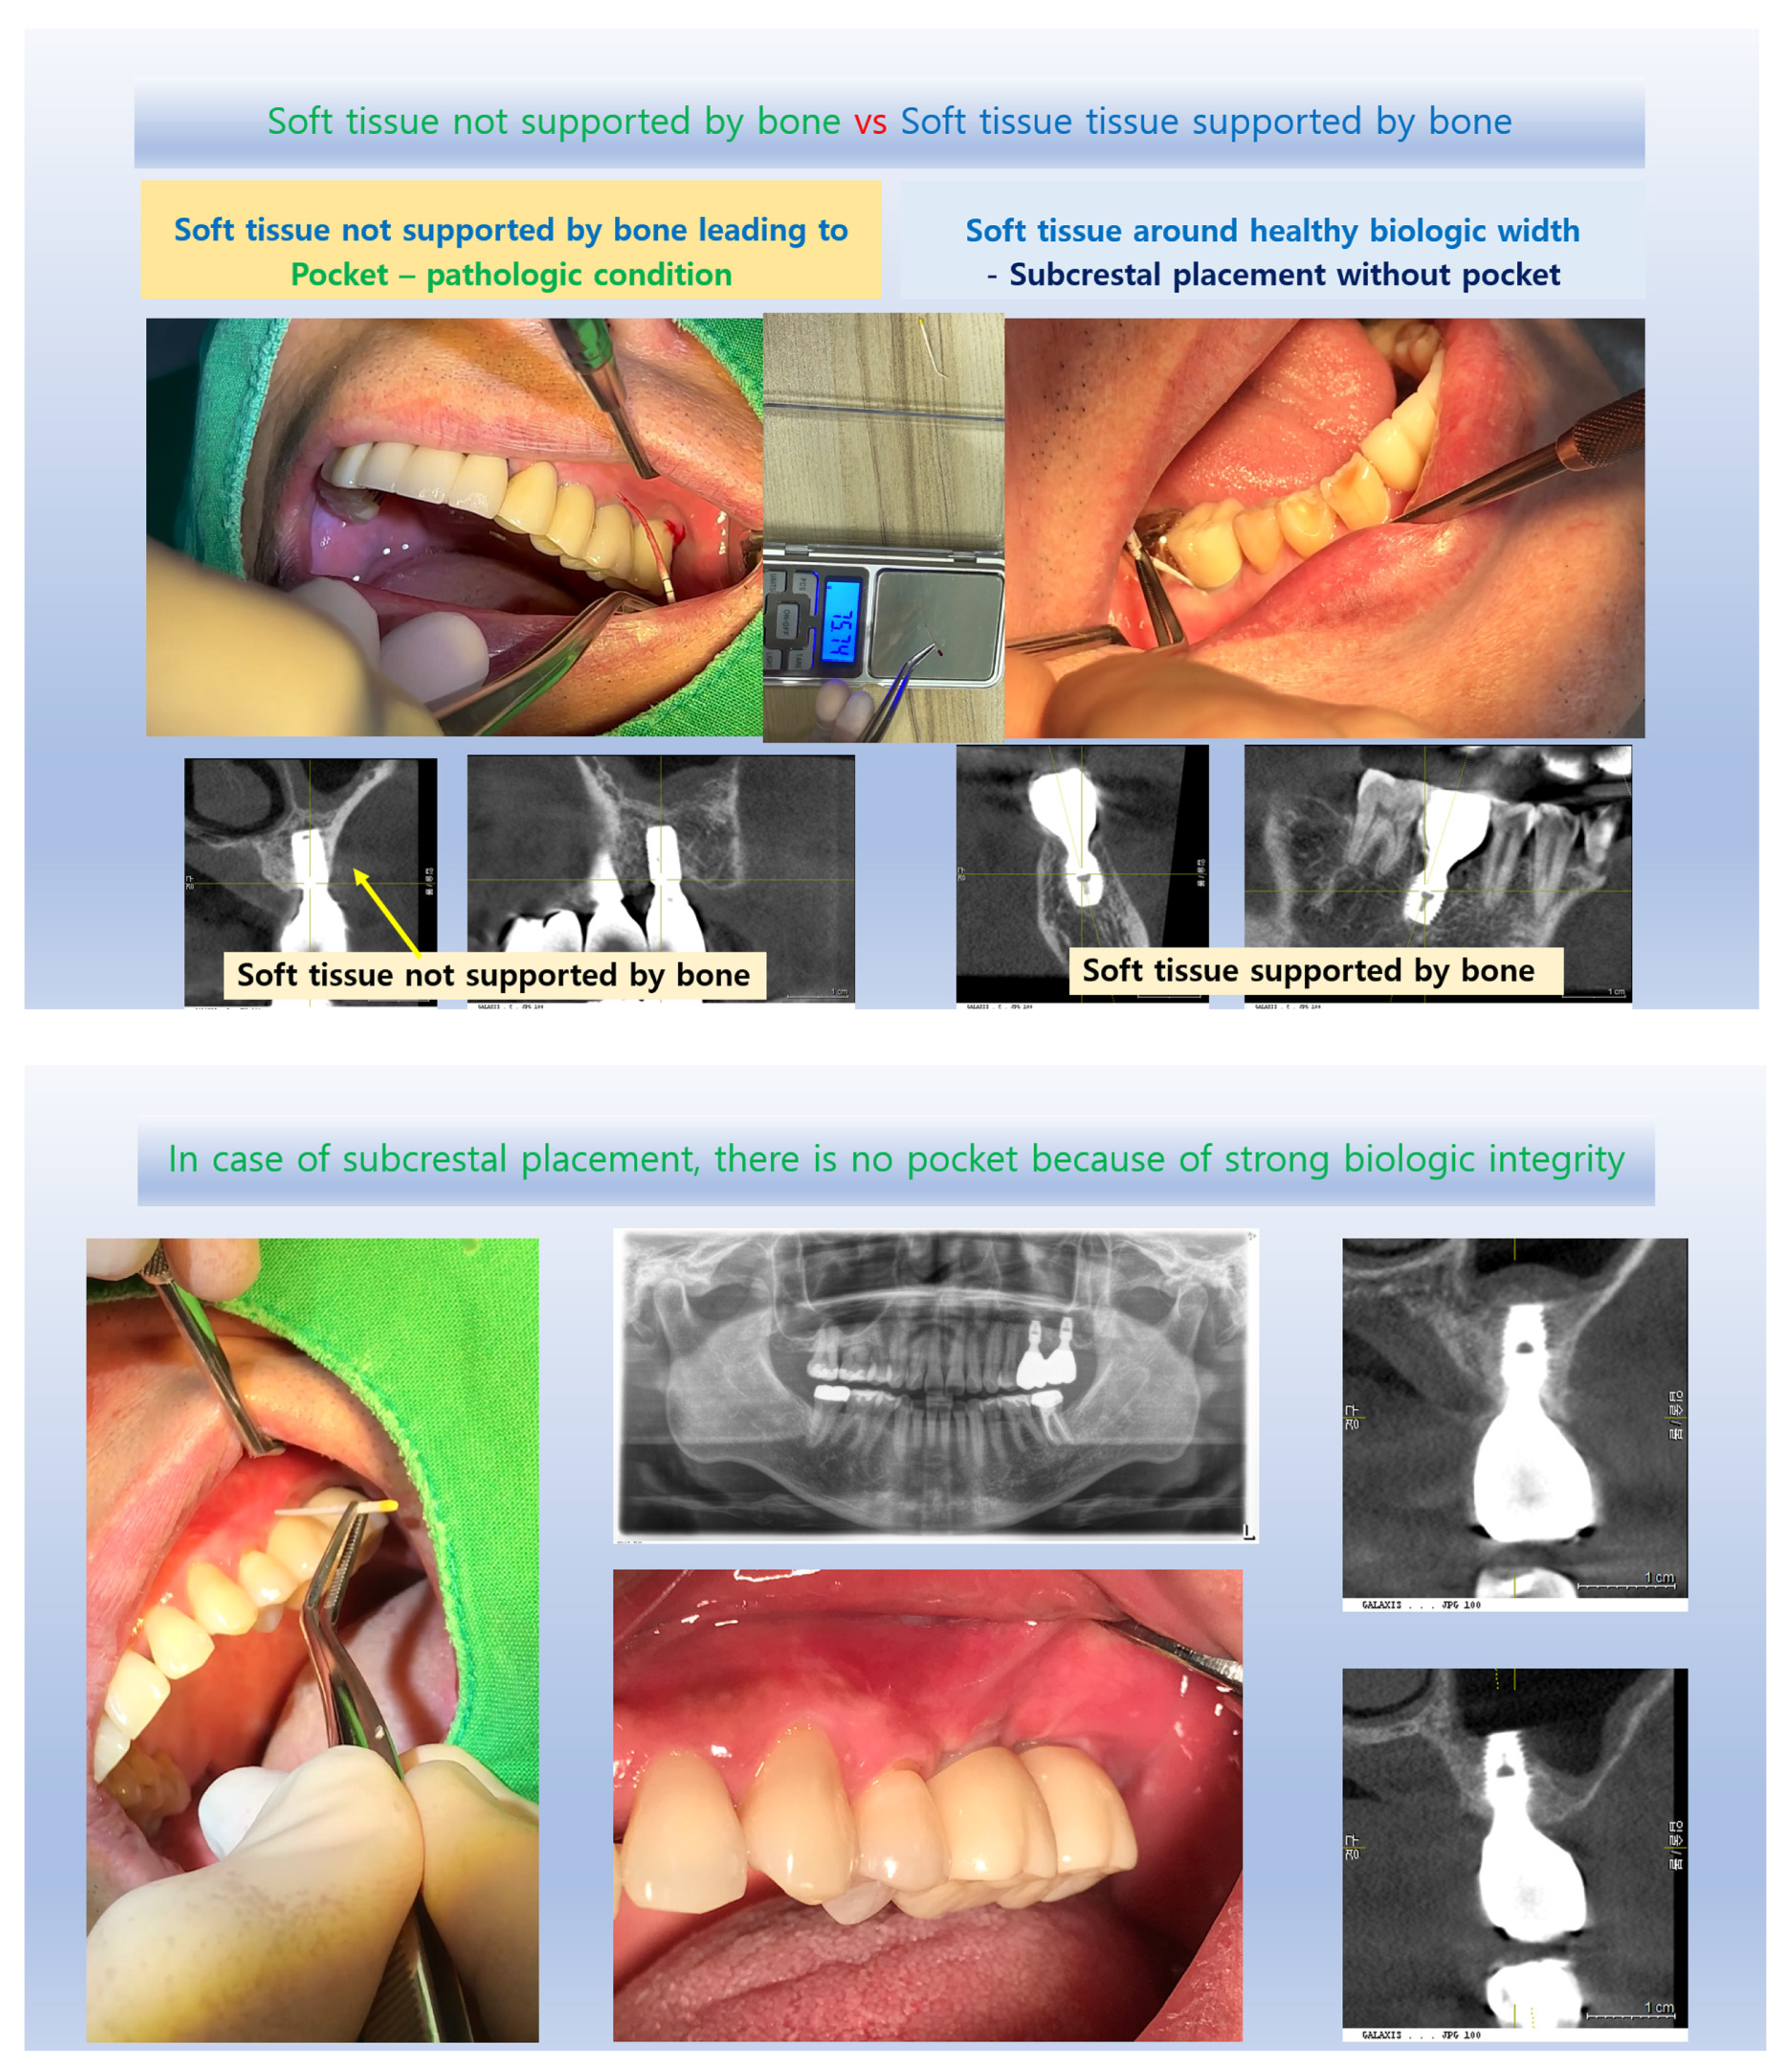

Figure 13. Unlike a natural gingival sulcus, which is a normal anatomical structure when the periodontium is healthy, a periodontal pocket indicates pathological deepening and is characterized by inflammation, bone destruction, and detachment of the junctional epithelium^[21]. This difference is crucial in dental practice, as the mere measurement of depth can predispose clinicians to judge the periodontal state as compromised. However, this perspective may be a preconception when analyzing implants, where a longer soft tissue transitional area (sometimes misinterpreted as a pathologic pocket) is often considered undesirable despite clinical evidence showing stable results in deeply placed implants.

Three-Dimensional Analysis and Subcrestal Implant Placement: The advent of Cone Beam Computed Tomography (CBCT) and its widespread use in implantology have shown that many implants are placed subcrestally, at least partially, without causing distinguishable pathological issues compared to epi-crestally placed implants^[12]. A lack of systematic methods for analyzing the submucosal soft tissue around subcrestally placed implants in a three-dimensional way likely contributes to unfounded pessimistic views. Three-dimensional soft tissue analysis (3DSTA) is particularly vital for subcrestal placements known to help reduce bone loss incidence^[1,22,23,24,25]. This technique also supports the creation of more natural-looking prostheses by providing sufficient space to offset the diameter difference between crowns and abutment-fixture connections, ensuring an appropriate emergence profile. Some authors have pointed out the limitations of two-dimensional analysis in studying implants and have suggested using micro-computed tomography for more detailed and accurate assessments^[26].

The Strengthening Effect of the Transitional Zone as a Biological Barrier

The absence of crestal bone change often signifies one of the best outcomes for implants. Traditionally, changes in crestal bone surrounding implants have been extensively studied. However, few reports have analyzed these changes in three-dimensional ways. Subcrestal placement of implants has been reported to offer advantages in terms of bone changes^[27,28]. Despite some negative reports about subcrestal placement techniques, these variations can often be attributed to different clinical approaches. For instance, deeply placed implants with excessive distance between soft tissue and abutments may lead to bone resorption due to inadequate mechanical sealing by the soft tissue. Additionally, if excessive cement remnants are not properly removed in subcrestally placed cases, they may lead to peri-implantitis. Previous studies have also included implants with external hex connection designs or matching platform designs, which may affect the relationship between fixture depth and bone loss.

The cases discussed in this article demonstrate the benefits of subcrestal implant placement, particularly when the distance between submucosal implant components and submucosal soft tissue is maintained closely at the Transitional Zone (TZ) and when the extraoral cementation technique effectively addresses issues with excessive cement remnants. Natalia Palacios-Garzon highlights internal connection and platform switching as positive factors for subcrestal placement. Muhammad H.S. Saleh reported that a subcrestal Implant-Abutment Junction (IAJ) position results in slightly less crestal bone loss compared to both supracrestal and equicrestal positions. It can be suggested that the soft tissue around the subcrestal implants may have a strengthening effect on the biologic width^[8,28].